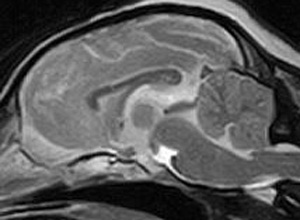

けいれん発作が出るワンちゃんが来院されました。MRI検査では脳に構造上の異常を認めず、脳脊髄液検査でも異常を認めず、特発性てんかんとの診断でお薬での治療となりました。発作は現在のところ、お薬で良好にコントロールされています。